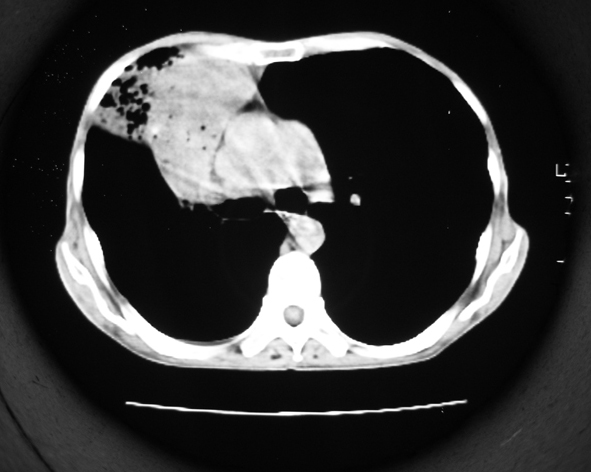

男53岁,咳嗽气短,以往身体健康.

右肺上叶多发多形态空洞及增殖灶,可见团块钙化,胸膜肥厚、粘连,考虑继发型肺结核可能性大

1.右肺上叶干酪性肺炎,2。肺气肿,肺大泡

右肺上中叶结核干酪性肺炎

右肺中上叶干酪性肺炎。

支持右上肺继发性肺结核并干酪性肺炎,右肺大泡,左肺代偿性气肿。